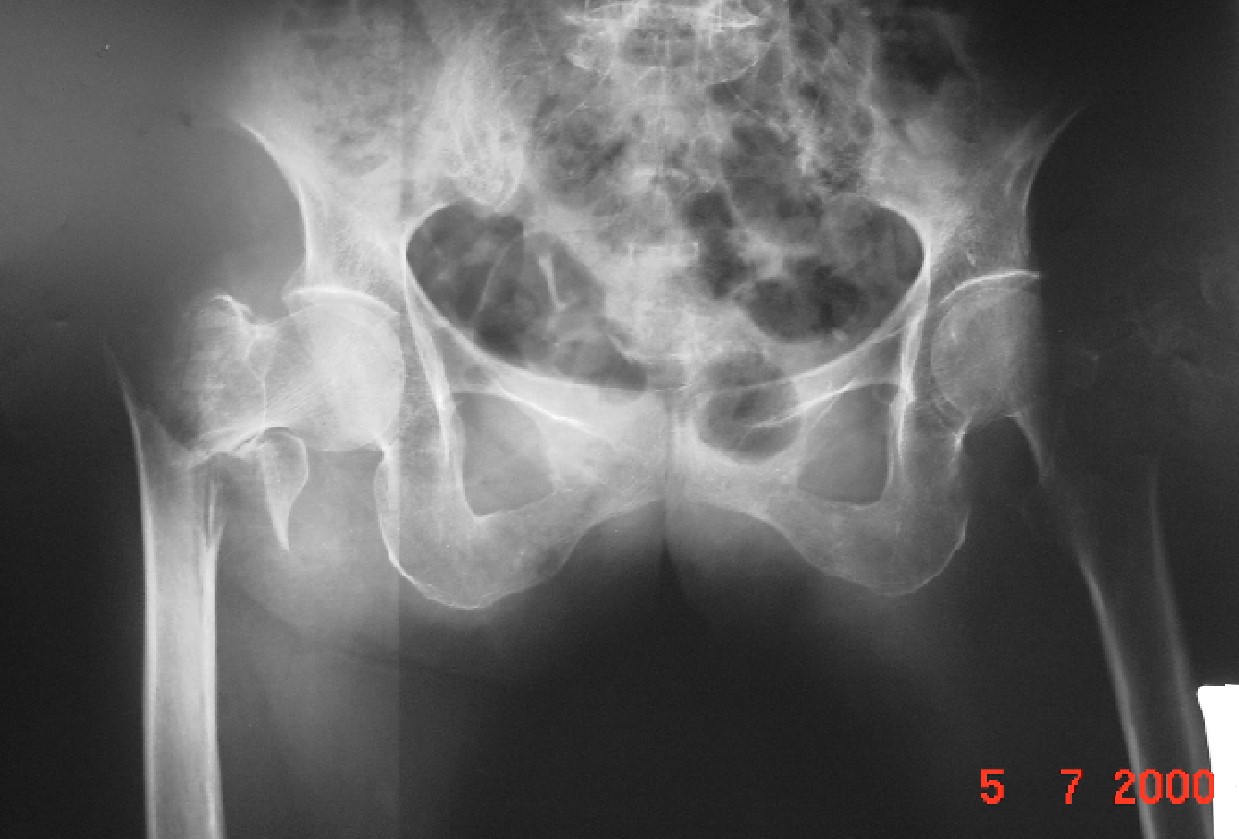

ภาพแสดงกระดูกสันหลังยุบจากโรคกระดูกพรุน

ภาพแสดงกระดูกสันหลังหักจากโรคกระดูกพรุน